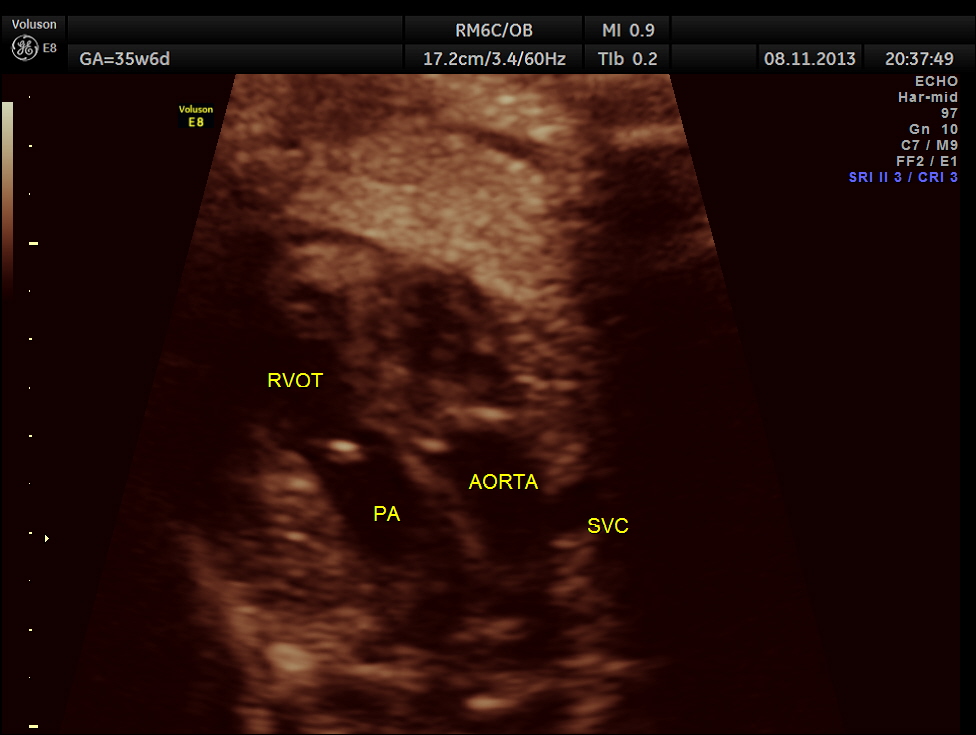

The scan was repeated at 36 weeks of gestation.